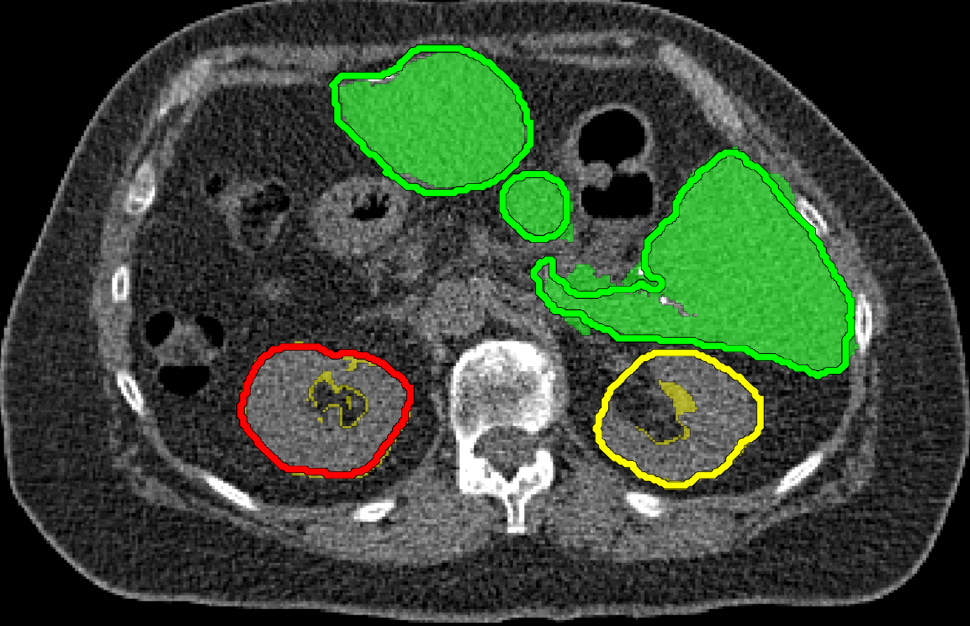

We applied our method on PET-CT scans of three different subjects to segment their liver, left kidney, right kidney and the background. Although we applied our method and Potts model on the 3D volumes we only show the results on a few representative slices from each volume in Fig.11. Also, the results of different methods for each subject were computed using the same smoothness. We can see from the last two rows which compare our method to Potts, using Hedgehogs constraints enabled us to avoid geometrically incorrect segmentations, e.g. one liver inside the other (last-row middle), or parts of left kidney is between the right kidney and liver (last-row right). Furthermore, for test subjects 1 and 2 the kidneys and background were poorly segmented by Potts model, e.g. most of the kidneys were segmented as background for test subject 1. Potts poor performance is due to the large overlap between the kidneys and background color models. This overlap resulted in an in-discriminative data term for Potts to properly separate them. This issue becomes worse in iterative frameworks where color models are re-estimated based on current segmentation. To be specific, if at any iteration Potts model resulted in a bad segmentation then re-estimating the color models will bias them towards the bad segmentation and subsequent iterations worsen the results. Comparing our results for subjects 1 and 2 to Potts model shows that our method is less prone to the aforementioned issue as we forbid undesirable segmentations, i.e. those that do not respect shape constraints.

| Subject 1 | Subject 2 | Subject 3 | |||

| Our method (Hedgehogs Shapes + Potts) | ![]() |

|

Potts |

For quantitative comparison, Table 1 lists for each organ of a subject the Score, Precession and Recall measures of our method and Potts model where For the kidneys, our method clearly out performed Potts model, e.g. note Potts model poor precision/recall for subjects 1 and 2. For the liver, both methods performed comparably.